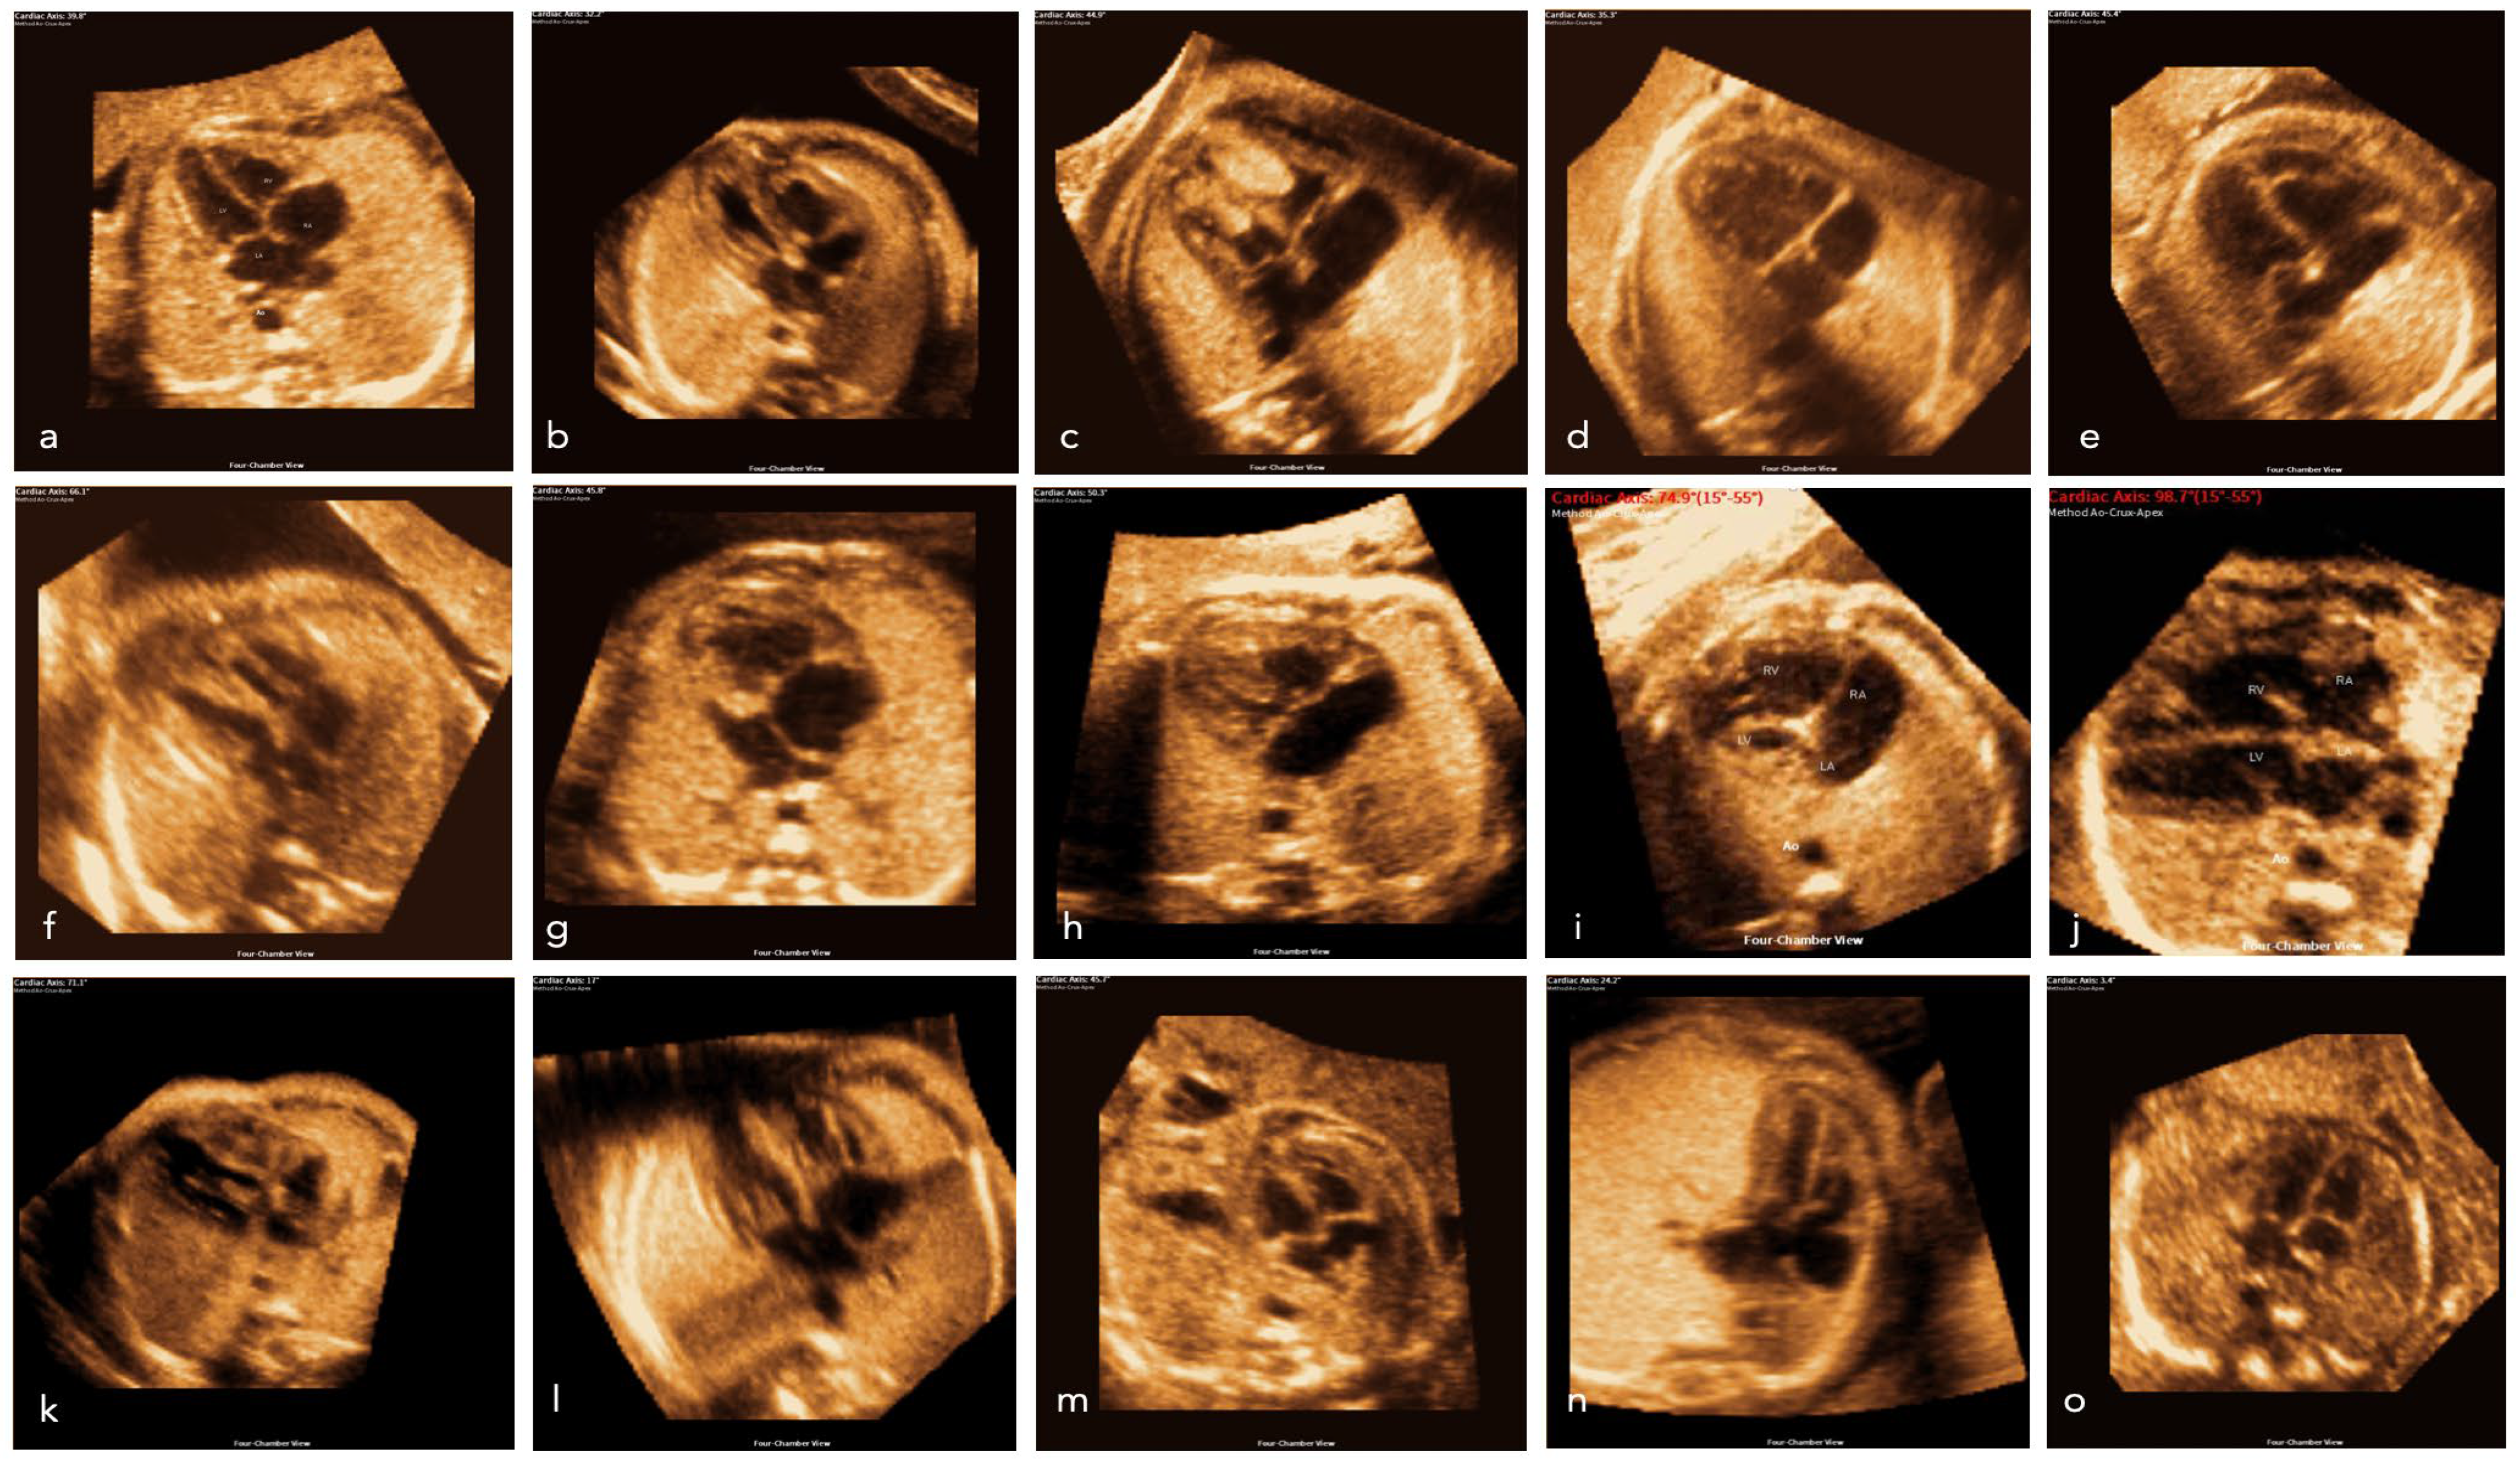

- Yeo, L.; Romero, R. Fetal Intelligent Navigation Echocardiography (FINE): A novel method for rapid, simple, and automatic examination of the fetal heart. Ultrasound Obstet. Gynecol. 2013, 42, 268–284. [Google Scholar] [CrossRef] [PubMed]

- Yeo, L.; Romero, R. New and advanced features of fetal intelligent navigation echocardiography (FINE) or 5D heart. J Matern Fetal Neonatal Med. 2022, 35, 1498–1516. [Google Scholar] [CrossRef] [PubMed]

- Wolter, A.; Kawecki, A.; Stressig, R.; Ritgen, J.; Degenhardt, J.; Enzensberger, C.; Axt-Fliedner, R. Fetal Cardiac Axis in Fetuses with Conotruncal Anomalies. Ultraschall Med. 2017, 38, 198–205. [Google Scholar] [CrossRef]

- Zhao, Y.; Edington, S.; Fleenor, J.; Sinkovskaya, E.; Porche, L.; Abuhamad, A. Fetal cardiac axis in tetralogy of Fallot: Associations with prenatal findings, genetic anomalies and postnatal outcome. Ultrasound Obstet. Gynecol. 2017, 50, 58–62. [Google Scholar] [CrossRef]

- Jung, Y.J.; Lee, B.R.; Kim, G.J. Efficacy of fetal cardiac axis evaluation in the first trimester as a screening tool for congenital heart defect or aneuploidy. Obstet. Gynecol. Sci. 2020, 63, 278–285. [Google Scholar] [CrossRef]